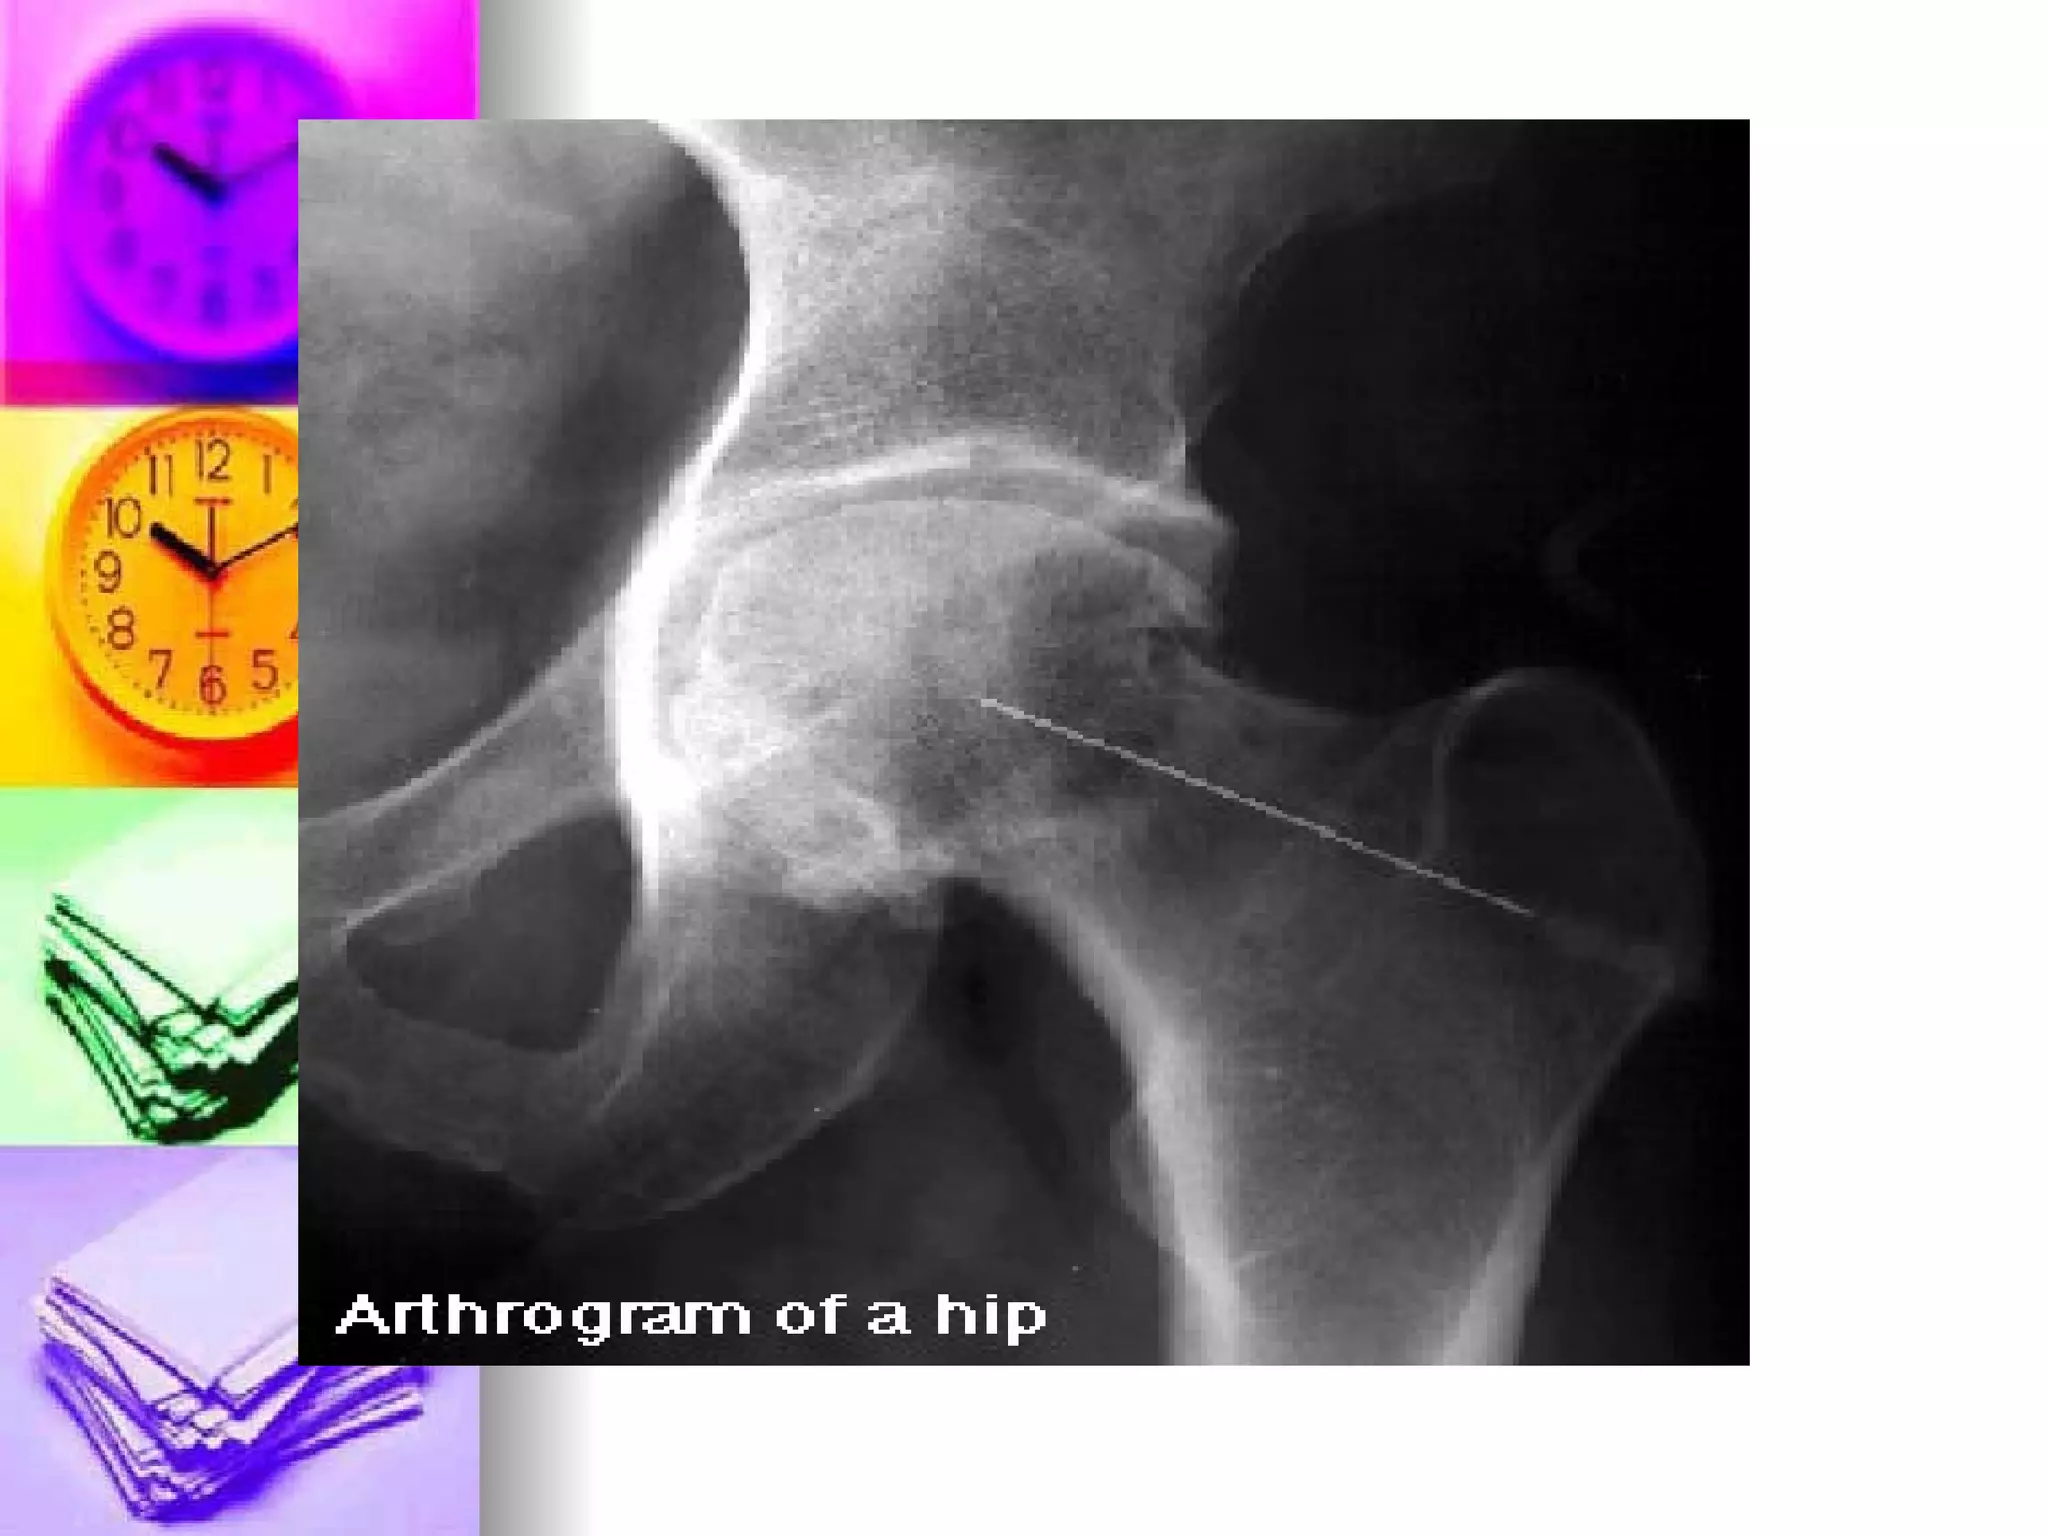

Arthrogram X-ray visualization of the joint after introduction of contrast medium Pre-test: consent, allergy to seafoods Post-test: Dressing over puncture site and limit joint activity

Arthrogram X-ray visualizationof the joint after introduction of contrast medium Pre-test: consent, allergy to seafoods Post-test: Dressing over puncture site and limit joint activity